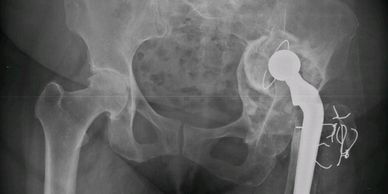

Mirá cómo recuperamos la movilidad en un caso de artrosis severa y deformidad acetabular mediante tecnología 3D de alta precisión. Planificación preoperatoria en 3D para cirugía de cadera con artrosis severa e importante deformidad acetabular. Se imprimieron biomodelos en 3D y guías para la correcta colocación de los componentes protésicos. De esta manera, se logró restaurar la longitud de las piernas y se eliminó el dolor invalidante que presentaba el paciente.

Cirugía compleja de reemplazo total de cadera.

Paciente con artrosis severa y deformidad ósea que dificultaba la colocación acetabular. Con tomografía realizamos planificación 3D y diseñamos una guía quirúrgica personalizada impresa en 3D. En quirófano replicamos el plan: posicionamiento preciso del componente y restauración del centro de rotación. La tecnología 3D aporta más precisión, seguridad y predictibilidad en casos complejos.